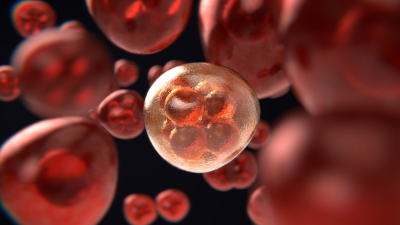

Εξέταση αίματος ανιχνεύει 50 διαφορετικούς τύπους καρκίνου, σύμφωνα με τον NHS

Μελέτη σοκ συνδέει τα γαλακτοκομικά προϊόντα με τον κίνδυνο εμφάνισης καρκίνου

Μoderna: Έτοιμα μέχρι το 2030 εμβόλια κατά του καρκίνου και καρδιακών παθήσεων

Νέα εξέταση αίματος «προβλέπει» τον καρκίνο ένα χρόνο πριν καν σχηματιστεί